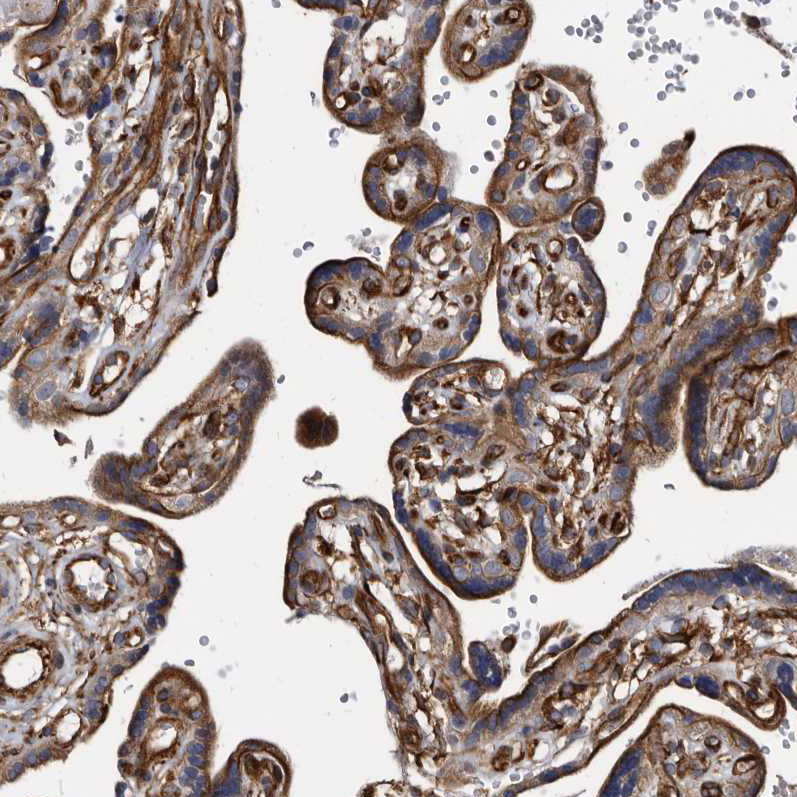

Immunohistochemical staining of human prostate shows strong cytoplasmic positivity in smooth muscle cells.